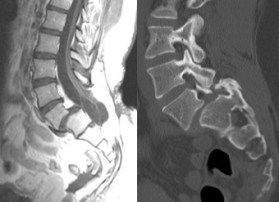

- anomalies rachidiennes : canal étroit, spondylolisthésis

attention, il existe souvent chez l’adulte un canal lombaire étroit associé,

parfois une lyse isthmique ; cette dernière ne nécessite pas forcément de prise en charge spécifique. la laminectomie doit être précautionneuse car le rachis lombaire bas contient la moelle, et non la queue de cheval.